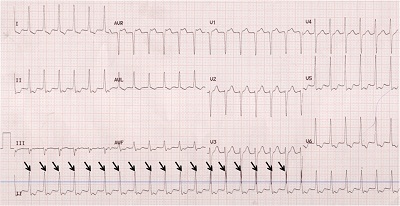

ECG where the heart is going slowly (bradycardia): On this ECG the spikes (marled with arrows) are a long way apart and the heart rate is very slow - less than 30 beats per minute.

Example of an ECG where the heart is going very slowly (bradycardia)